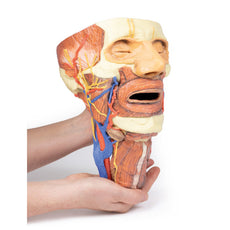

3D Printed Head and Visceral Column of the Neck

These items normal warranty are two years, however the warranty doesn’t cover “wear and tear”. The manufacturer does have 100% quality control on these models.

The models are very detailed and delicate. With normal production machines you cannot realize such details like shown in these models.

The printer used is a color-plastic printer. This is the most suitable printer for these models.

The plastic material is already the best and most suitable material for these prints. (The other option would be a kind of gypsum, but this is way more fragile. You even cannot get them out of the printer without breaking them).The huge advantage of the prints is that they are very realistic as the data is coming from real human specimen. Nothing is shaped or stylized.

The users have to handle these prints with utmost care. They are not made for touching or bending any thin nerves, arteries, vessels etc. The 3D printed models should sit on a table and just rotated at the table.

The models are very detailed and delicate. With normal production machines you cannot realize such details like shown in these models.

The printer used is a color-plastic printer. This is the most suitable printer for these models.

The plastic material is already the best and most suitable material for these prints. (The other option would be a kind of gypsum, but this is way more fragile. You even cannot get them out of the printer without breaking them).The huge advantage of the prints is that they are very realistic as the data is coming from real human specimen. Nothing is shaped or stylized.

The users have to handle these prints with utmost care. They are not made for touching or bending any thin nerves, arteries, vessels etc. The 3D printed models should sit on a table and just rotated at the table.